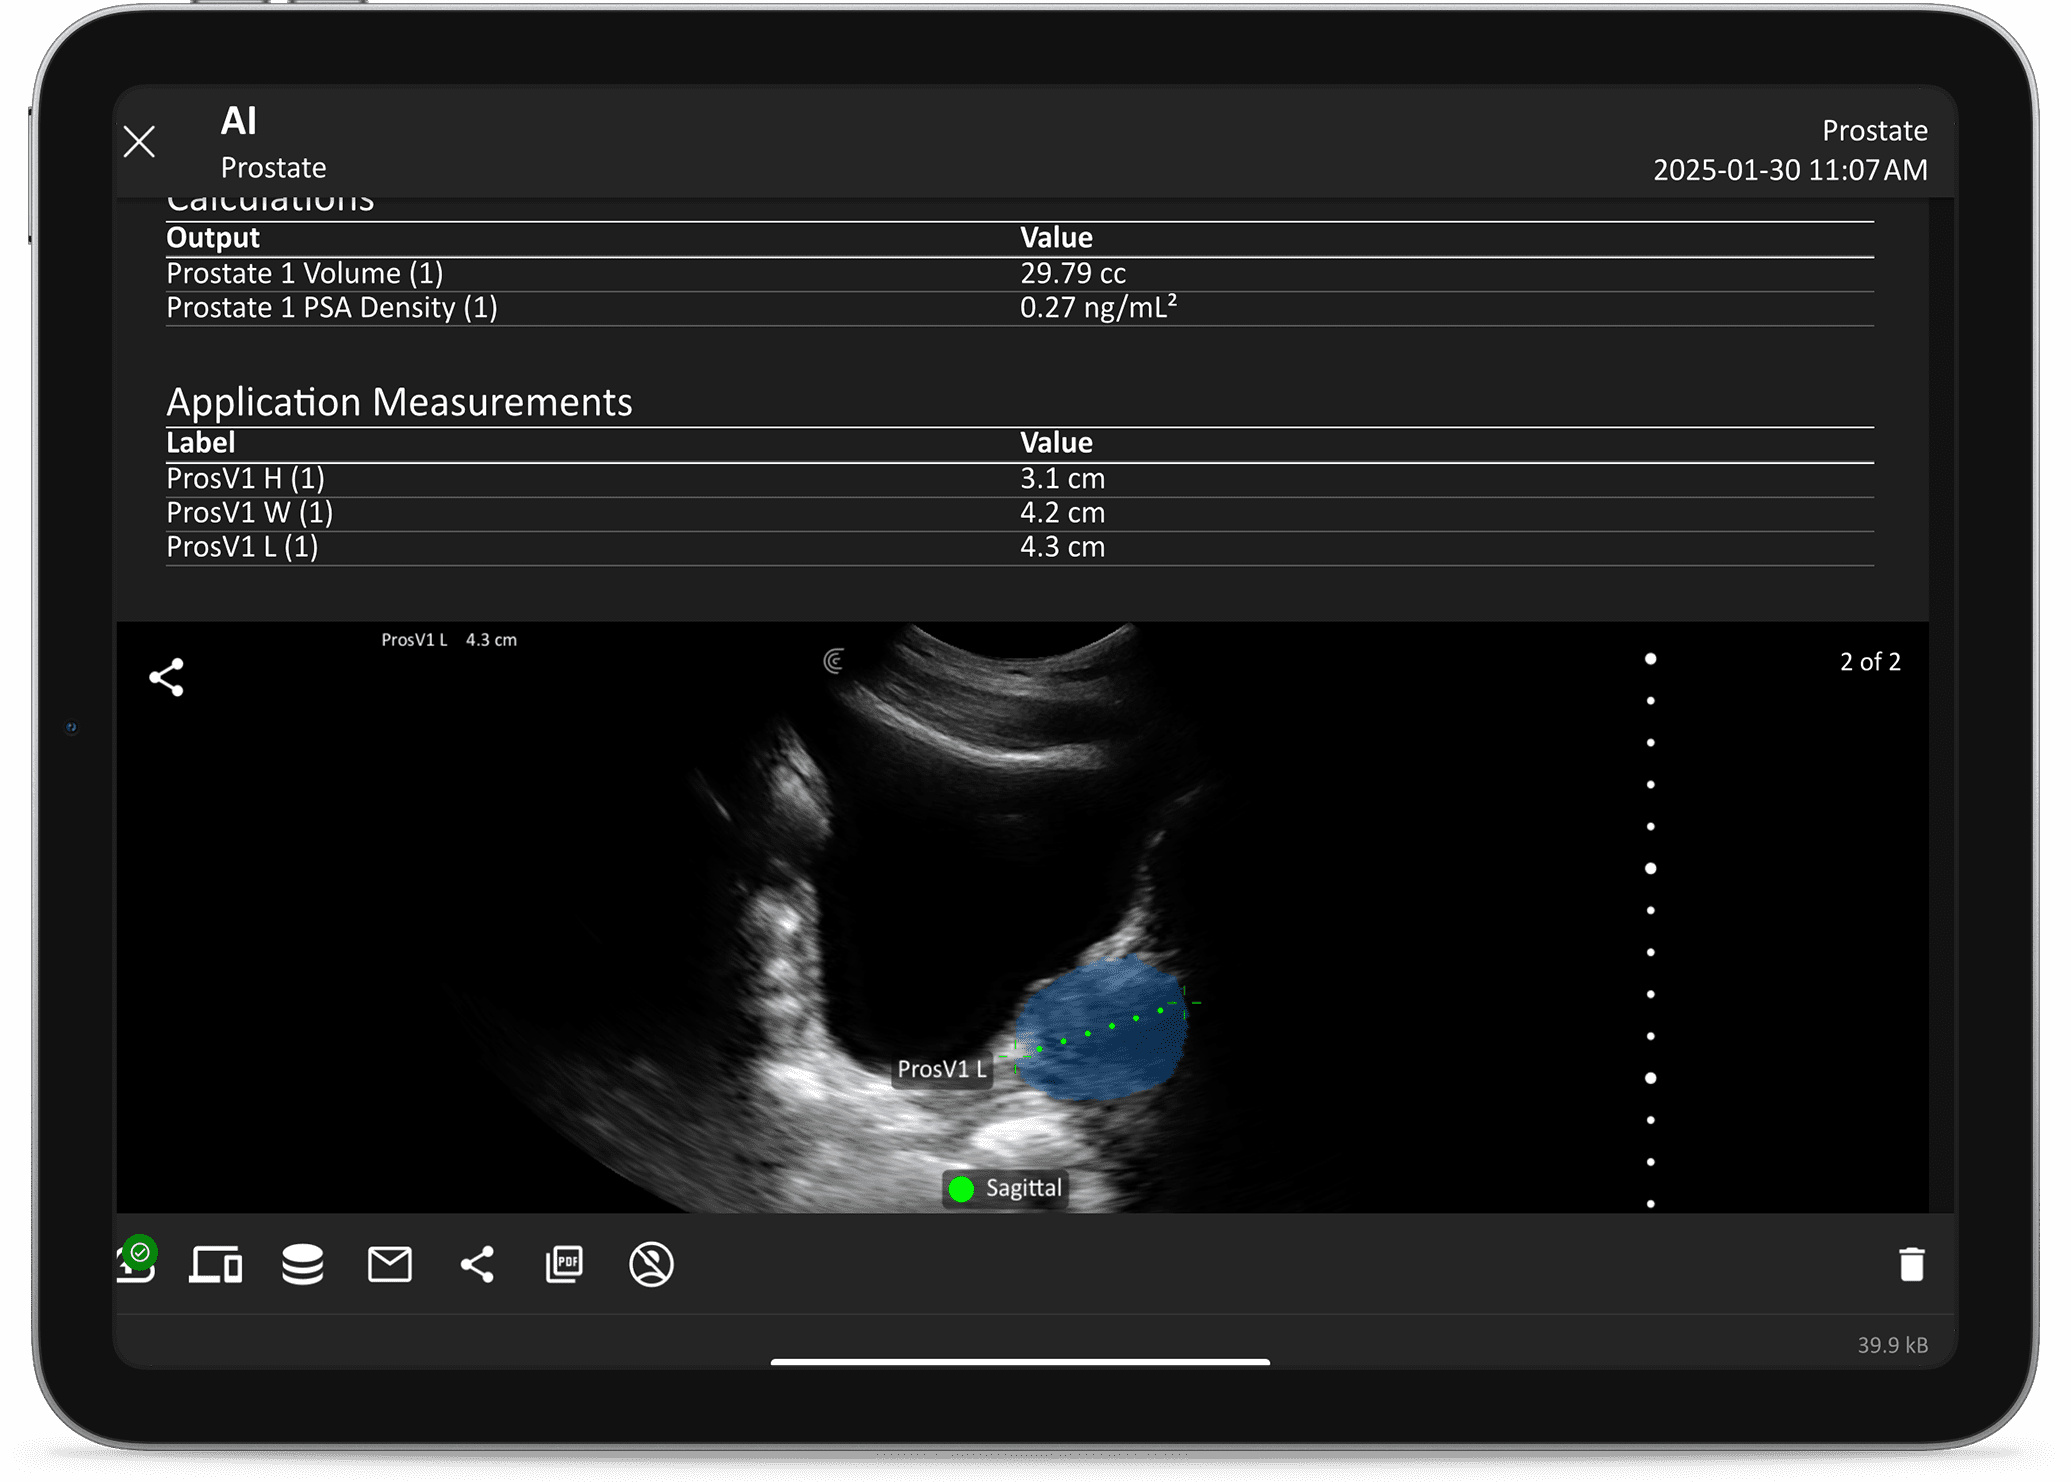

During an exam, clinicians can activate Prostate AI with a tap in the Clarius App on a smartphone or tablet. The tool automatically highlights the prostate gland and, when the image is frozen, places calipers to measure volume. Clinicians can fine-tune the calipers manually for precision. The app also calculates PSA density using the entered PSA value and measured volume—supporting earlier, more informed detection of prostate cancer.